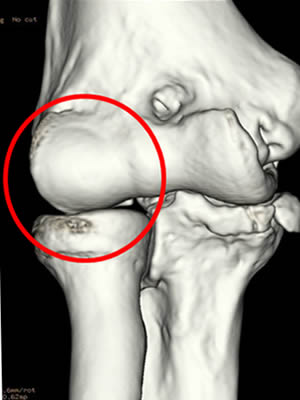

下の図は,正常な肘(図1)と離断性骨軟骨炎を呈している肘(図2)です。

肘に繰り返し負担がかかると骨軟骨がはがれていきます(図2の○部)。

手術は肘または膝から採取した骨軟骨を肘のはがれた部分に移植し修復します。

図1:正常な肘 |

図2:離断性骨軟骨炎を呈した肘 |